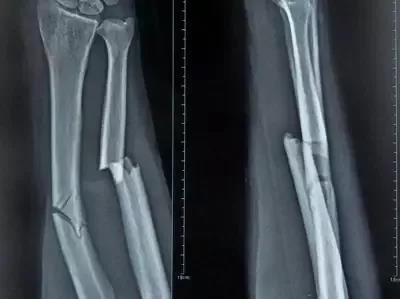

骨折痊愈过程一般分为3个时期:血肿形成期、骨痂形成期、骨痂改造期——即新生骨形成期。